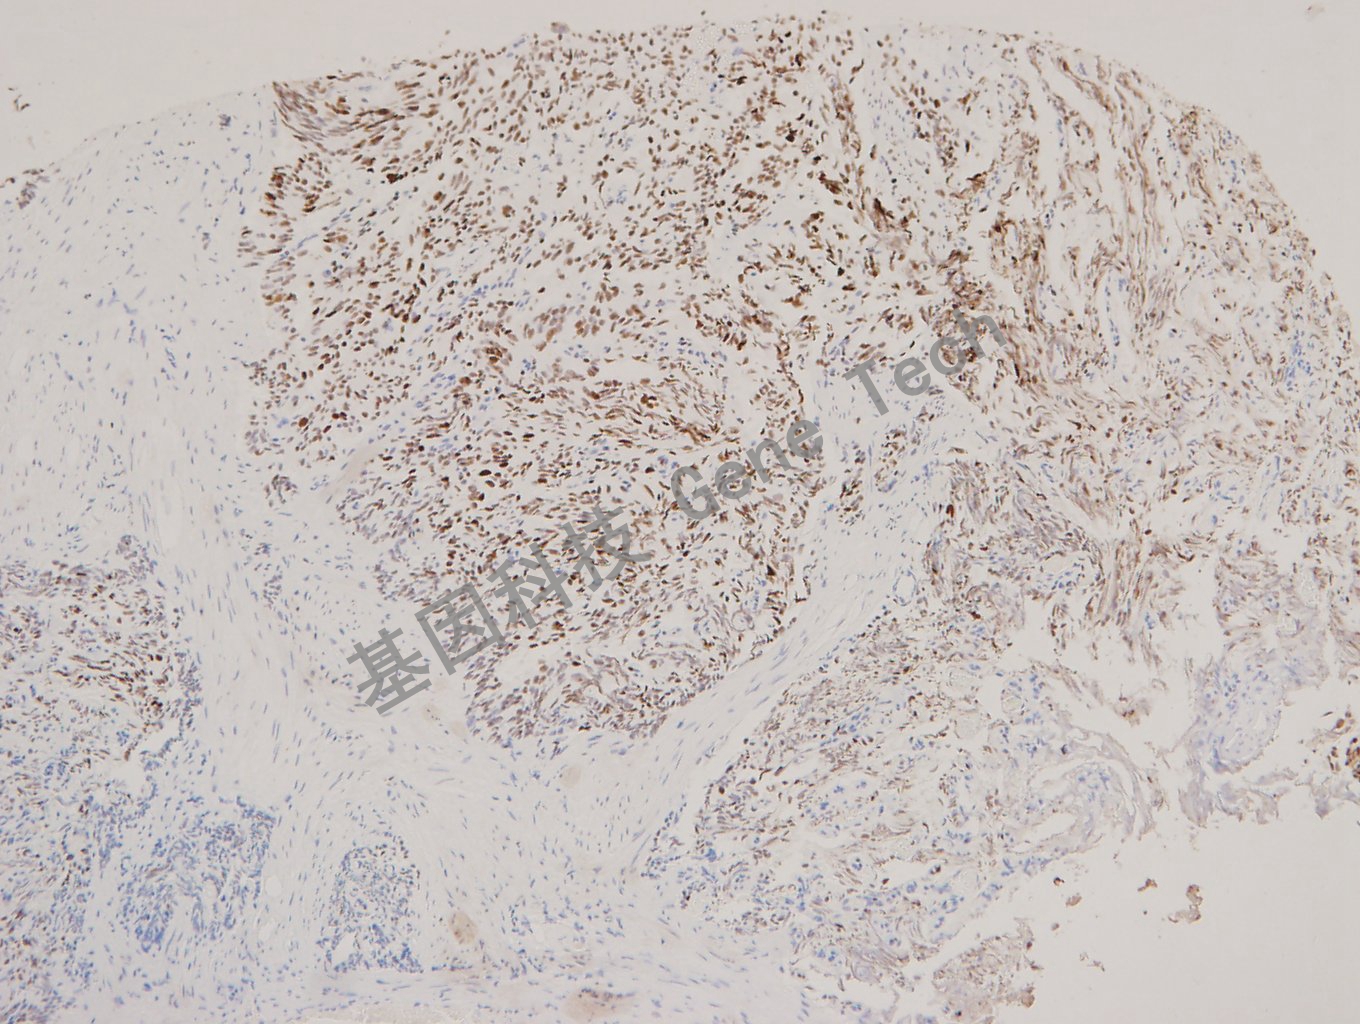

肺癌石蜡切片,用 MCM2(GT2316)染色,细胞核阳性,DAB显色。

结肠癌石蜡切片,用 MCM2(GT2316)染色,细胞核阳性,DAB显色。

前列腺癌石蜡切片,用 MCM2(GT2316)染色,细胞核阳性,DAB显色。

乳腺癌石蜡切片,用 MCM2(GT2316)染色,细胞核阳性,DAB显色。